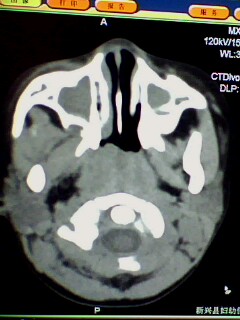

腺样体肥大,鼻窦炎。

腺样体肥大,副鼻窦炎症。支持!乳突尚未发育完全,加上位置不标准不好说。

1)鼻咽腺样体肥大。2)双侧上颌窦、双侧筛窦及双侧蝶窦炎症。